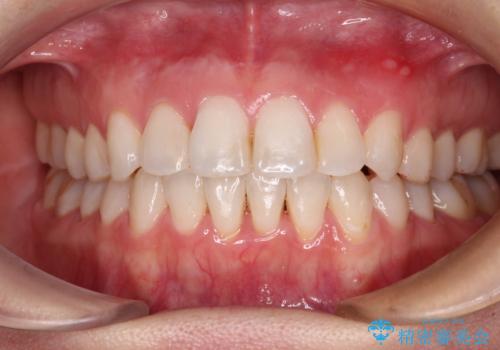

長年気にしていた前歯 インビザラインで目立たず改善

下顎前歯の叢生が顕著な場合、歯列改善後に歯と歯と歯肉の間にブラックトライアングルという隙間ができてしまいます。

軽減することはできますが、完全に解決することは矯正治療のみでは不可能なため、リスクとして事前に周知しておく必要があります。